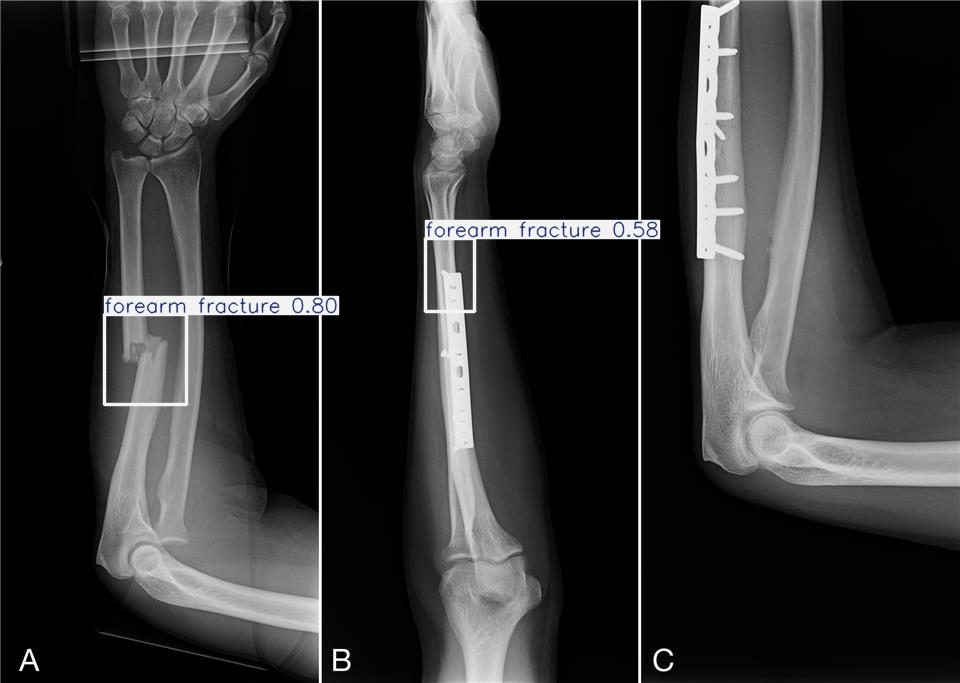

Fracture Detection & Localization

Detect Fractures in Real-Time

Analyze X-rays in real-time to detect fractures and highlight them with Box

Flag potential fracture zones and generate visual overlays to assist radiologists during diagnosis.